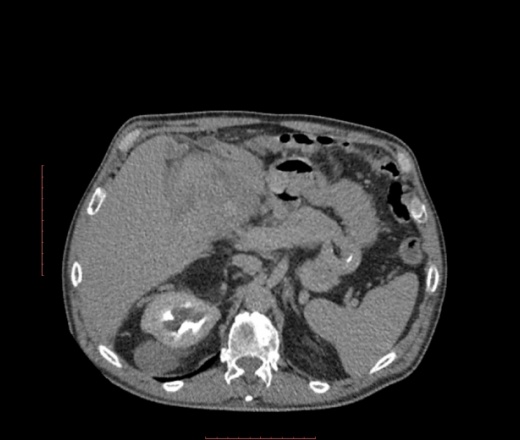

Пациент мужского пола 1950гр, на ирригографии после подозрения на опухоль кишечника, выявили образование смешающее петли кишечника.

В печени похоже на гемангиому, в малом тазу вижу изменения в паховом канале, в правом яичке.

Картинок совсем немного, попробуйте сделать серию изображений всей артериальной и верозной фазы, удалив каждую вторую картинку, потом еще раз каждую вторую, чтоб получилось 50-100 изображений по каждой фазе в отдельности. А так - ну вроде гемангиома печени, вроде мезенхимальная опухоль брюшной полости. Не ясно: по венозке гидронефроз или синусовые кисты, соотношение образования с печенью, жировой компонент ниже опухоли принадлежит ей (липосаркома) или нет и там просто жидкость.

Спасибо за совет. Добавил изображнеия. В почках кисты*. А какова связь образоваия с правой паховой областью?

Липосаркома, а вниз распространяется по околопочечным пространствам.

липосаркома разной степени дифференцииации